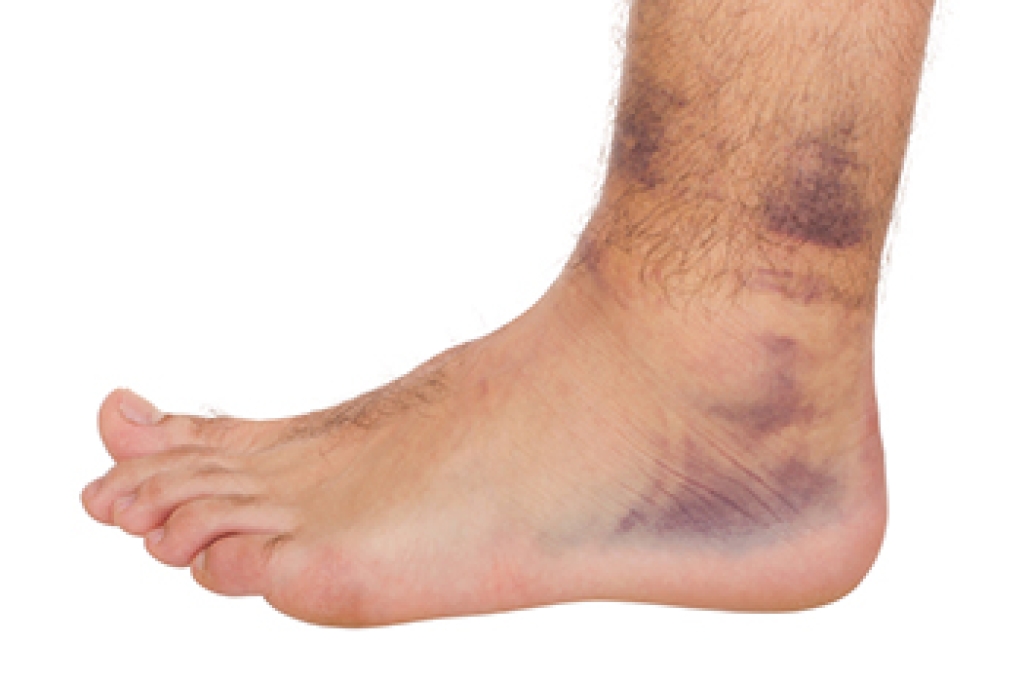

An ankle sprain might seem like a minor injury, but without proper care, it can lead to long-term instability and recurring issues. The ligaments in the ankle are designed to provide support and balance, but a sudden misstep, awkward landing, or quick pivot can overstretch or tear them. Many people assume a sprain will heal on its own, but rushing back to activity too soon can cause weakness and increase the risk of reinjury. Persistent swelling, pain, or difficulty bearing weight may indicate a more severe sprain that requires medical attention. Strengthening and balance exercises help prevent future sprains, while wearing supportive footwear adds protection. Ignoring a sprain can lead to chronic instability, making future injuries more likely. If pain lingers or mobility is compromised, it is strongly suggested that you see a podiatrist to ensure proper healing and prevent long-term damage.

Ankle sprains take place when the ligaments in your ankle are torn or stretched beyond their limits. There are multiple ways that the ankle can become injured, including twisting or rolling over onto your ankle, putting undue stress on it, or causing trauma to the ankle itself.